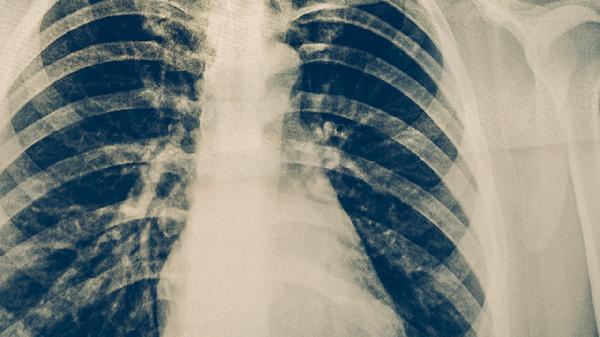

肺癌

肺癌傳染嗎在一起吃飯

肺癌傳染嗎在一起吃飯與肺癌患者吃飯是不會傳染的。腫瘤不會通過唾液傳染給別人的,所以肺癌病人的口水、食物等是不會傳染給別人的。肺癌是發(fā)病率和死亡率增長最快,對人群健康和生命威脅最大的惡性腫瘤之一。近50年來許多國家都報(bào)道肺癌的發(fā)病率和死亡率均明顯增高,男性肺癌發(fā)病率和死亡率均占所有惡性腫瘤的第一位,女性發(fā)病率占第二位,死亡率占第二位。建議可以多鍛煉自己的身體,飲食要搭配合理比如可以粗細(xì)糧的搭配,這樣人的身體需要的營養(yǎng)就會均衡,要注意多休息,出門的時候可以帶一個口罩,防止空氣污染物加重肺癌。